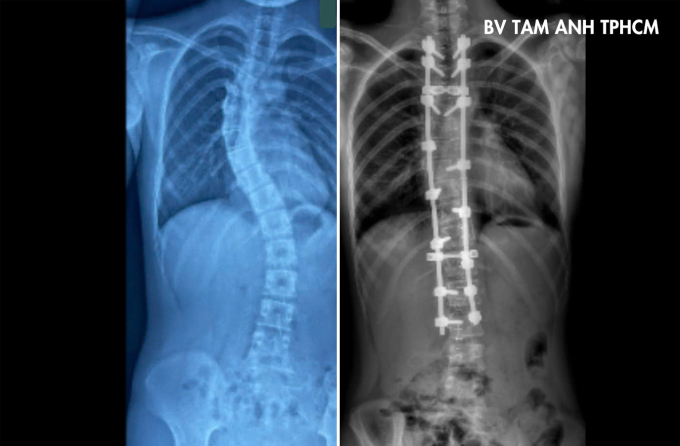

Phim chụp X-quang tình trạng cột sống bệnh nhi trước (trái) và sau phẫu thuật. Ảnh: Bệnh viện Đa khoa Tâm Anh

Sophea điều trị tại Campuchia hơn một năm, nay sang Việt Nam phẫu thuật. Kết quả chụp X-quang tại Bệnh viện Đa khoa Tâm Anh TP HCM cho thấy đoạn từ đốt sống ngực thứ 4 đến thứ 10 vẹo sang phải 57 độ, từ đốt sống ngực thứ 10 đến đốt sống lưng thứ 3 vẹo trái 40 độ, có dấu hiệu chèn ép phổi. Hai vai bệnh nhi lệch nhiều, gù lưng, khó rướn người, đau khi vận động mạnh.

Sau 4 giờ, 16 vít được sử dụng để nắn chỉnh phần cột sống trên về 17 độ và cột sống dưới về 15 độ. Ngày thứ hai sau mổ, Sophea có thể tự đi lại, hai vai cân bằng và dáng đi cải thiện rõ rệt. Tiên lượng sau hai tuần, bệnh nhi có thể sinh hoạt như bình thường. Bác sĩ khuyến khích bé tham gia các môn thể thao như đu xà, bơi lội, tránh các môn có tính đối kháng, và sinh hoạt đúng tư thế để tránh cong vẹo cột sống tái phát hoặc mắc biến chứng đau lưng sau mổ.